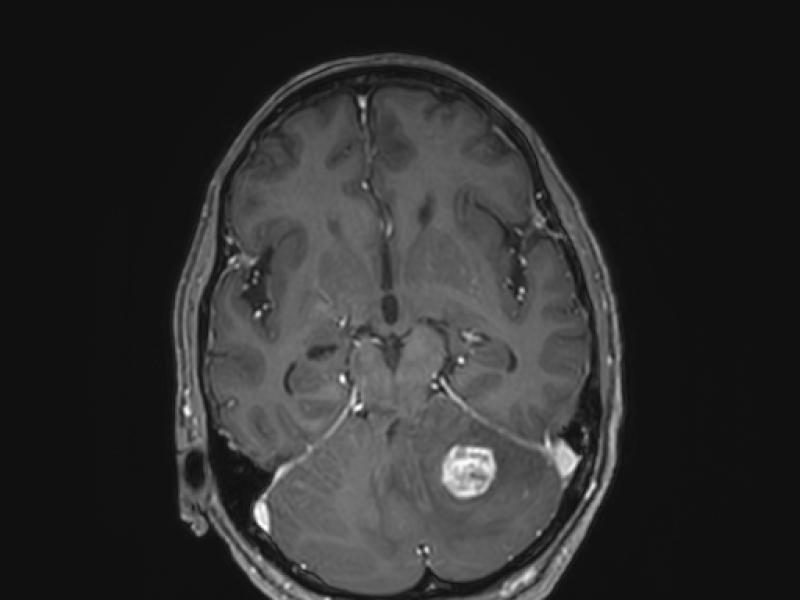

What's the diagnosis? By Dr. Angela Ugorets

A 64 yo female c/o dizziness. She has an unsteady gait